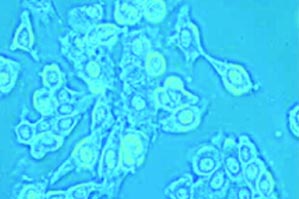

Do you see where this is going yet? The group sifted through a huge library of protein-tagged bacteriophages until they found one that was recognized by breast cancer cells. Then they mixed the phage-derived protein with a the nanocarrier containing a drug that kills breast cancer cells. The bacteriophage lodged itself inside the nanocarrier’s lipid membrane, as if it were a bacterial membrane, with the protein fragment dangling on the outside. Then they mixed these little guys with cancerous and non cancerous cells in a test tube and found that they attacked cancer cells and bypassed healthy cells.